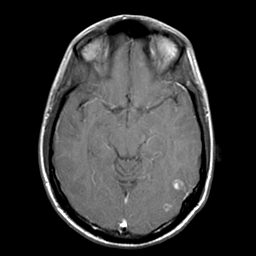

Sarcoma, MR Study #1 mr-gad -- Slice #9

[Home][Help][Clinical] Slice 9